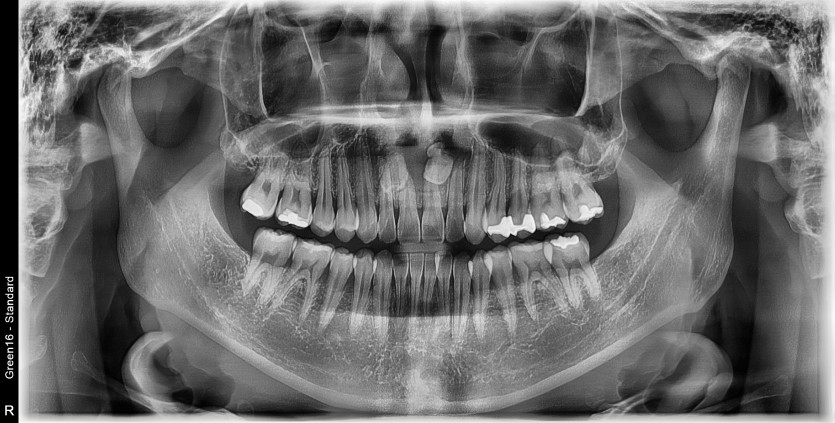

매복 과잉치와 낭종을 제거하고 치조골 이식을 진행하였습니다.